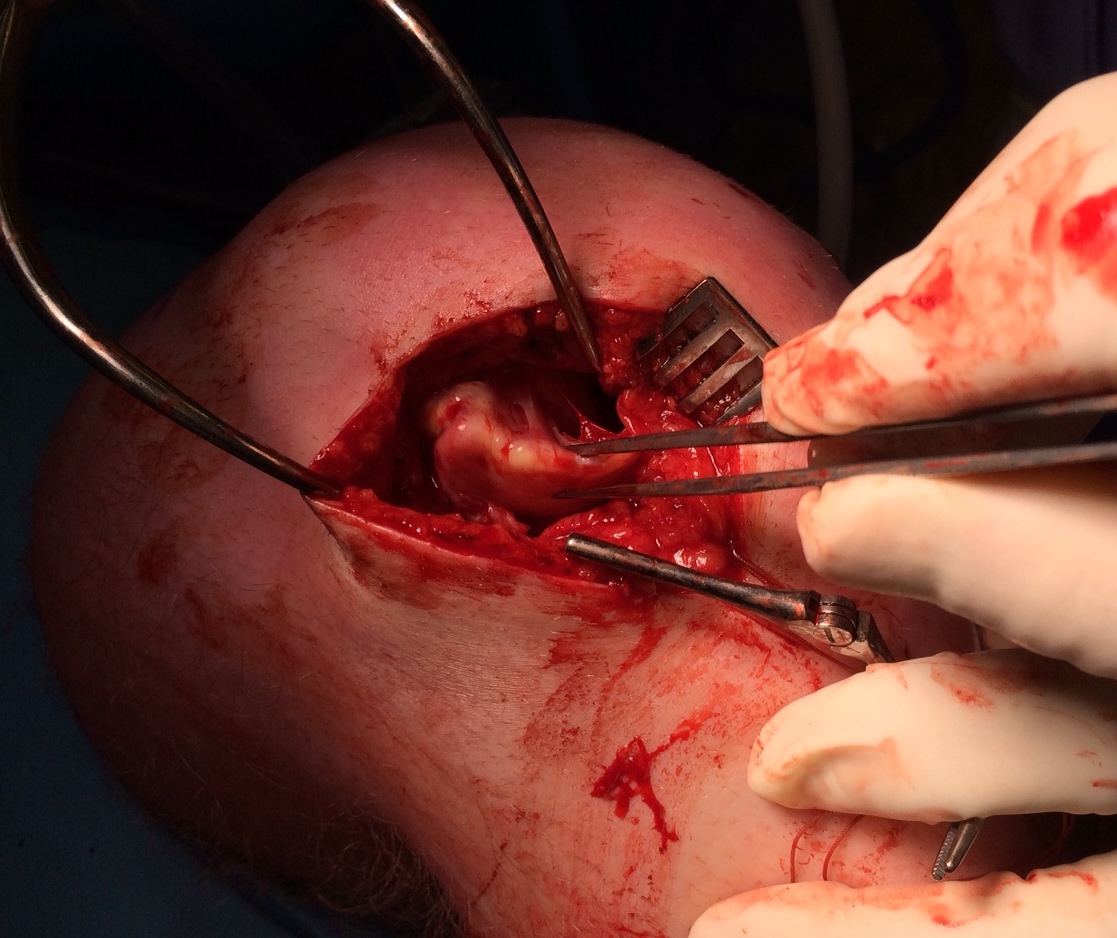

MFC unstable OCD